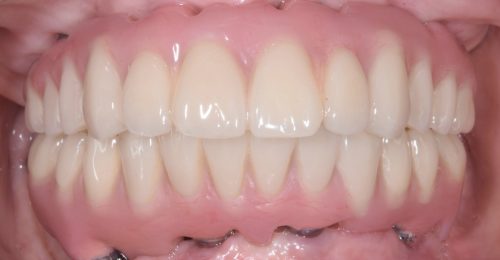

• 上顎インプラント3本とザイゴマ2本、下顎インプラント4本による上下オールオン4

術前

術後

年齢・性別 65歳・女性

治療期間 オペから上部セットまで6ヶ月、通院回数19回

治療費用 5,758,180円(税込)

治療内容 前歯のブリッジが取れ来院。下顎臼歯のデンチャーも使っていない状態。歯周病も重度で上下顎でしっかり噛みたいとインプラントを希望。